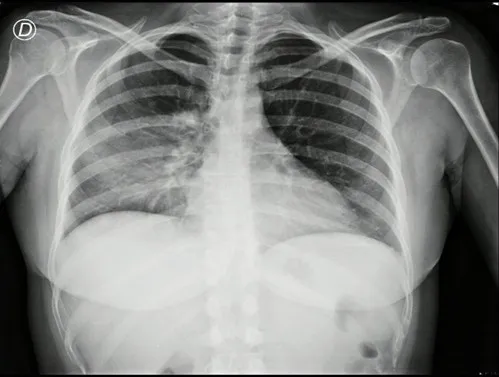

Radiografía de tórax de ingreso: Regular técnica. Senos costofrénicos libres. Evidencia de radio opacidad heterogénea en base pulmonar derecha sin grandes cambios con respecto a radiografías previas.

Imagen 5: Radiografía de tórax frente, presenta radiopacidad heterogénea en base pulmonar derecha.